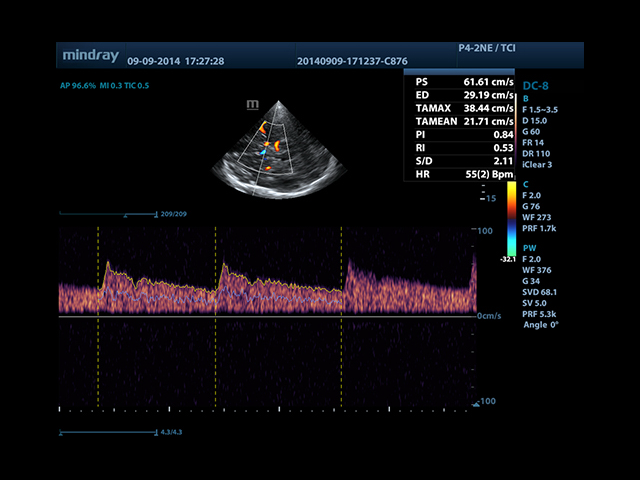

• Автоматическая трассировка допплеровского спектра с расчетом параметров и индексов

• Секторный датчик Mindray P4-2E